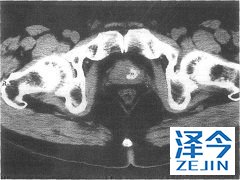

在有基线轻度(n=8)或中度(n=8)肝受损受试者和在8例有正常肝功能健康对照受试者中检查阿比特龙的药代动力学。对基线轻度肝受损患者无需剂量调整。

在基线中度肝受损患者中,减低推荐剂量:阿比特龙至250mg每天1次,如基线中度肝受损患者中,发生ALT或AST升高>5×ULN或总胆红素> 3×ULN终止阿比特龙治疗。未曾在基线严重肝受损患者中研究阿比特龙的安全性。这些患者不应接受阿比特龙。对治疗期间发生肝毒性患者,中断治疗和可能需要剂量调整。